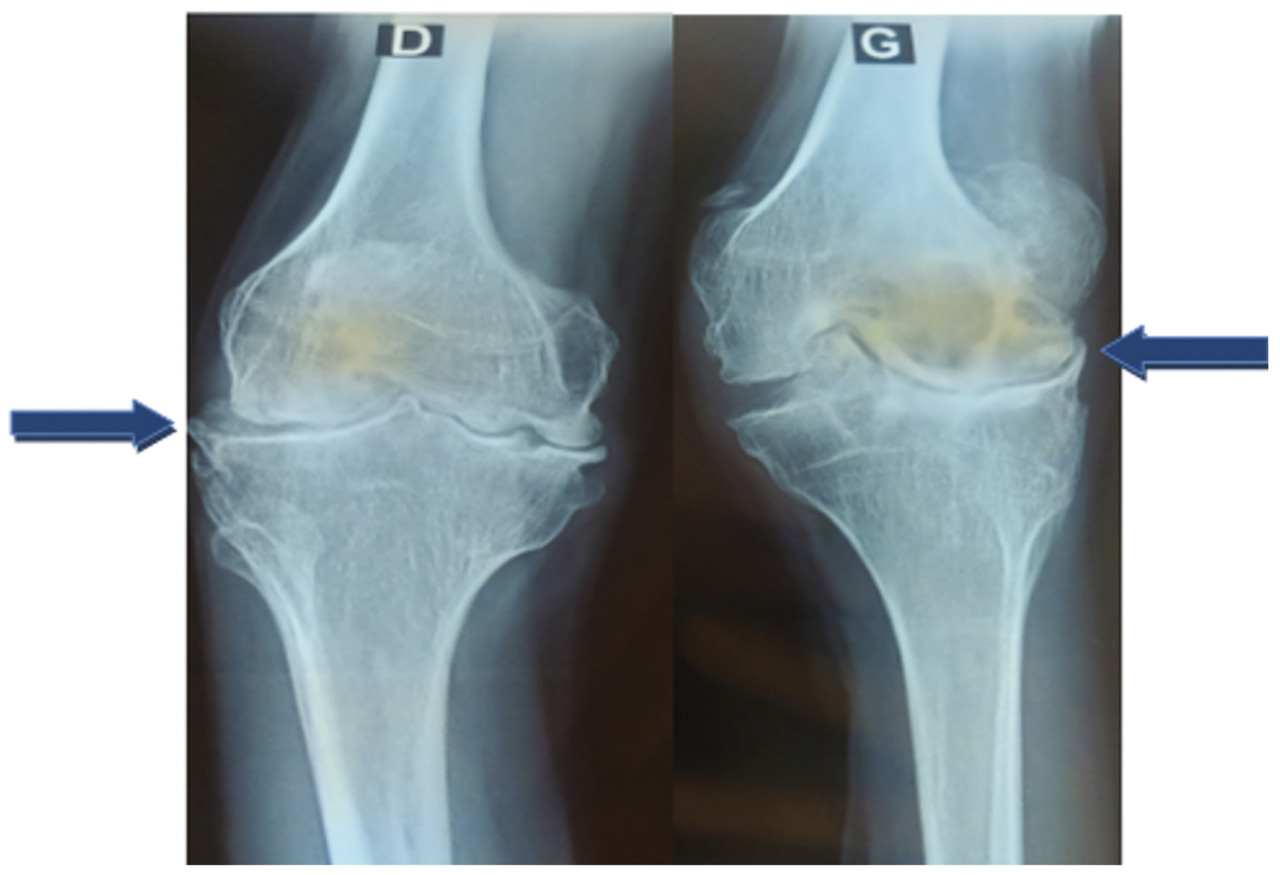

L’examen physique retrouve une hypertrophie articulaire du genou gauche avec un flessum irréductible des deux genoux, plus marqué à gauche, une atrophie du quadriceps et des muscles du mollet, une déformation avec perte de la dorsiflexion et de la flexion plantaire des chevilles (fig. 1 et 2 ). La protéine C-réactive est normale. Les radiographies des deux genoux et des deux chevilles révèlent respectivement une destruction articulaire et un ostéophyte de la partie antérieure de l’articulation talocrurale (fig. 3 et 4 ).

La radiographie standard reste l’examen de base pour rechercher des signes témoignant d’une hémarthrose et/ou d’une arthropathie hémophilique (tuméfaction synoviale, raréfaction osseuse périarticulaire, hypertrophie épiphysaire, pincement articulaire diffus, érosions marginales bien limitées, érosions et géodes centrales, stries d’arrêt de croissance, troubles de la croissance des os et déformations).6